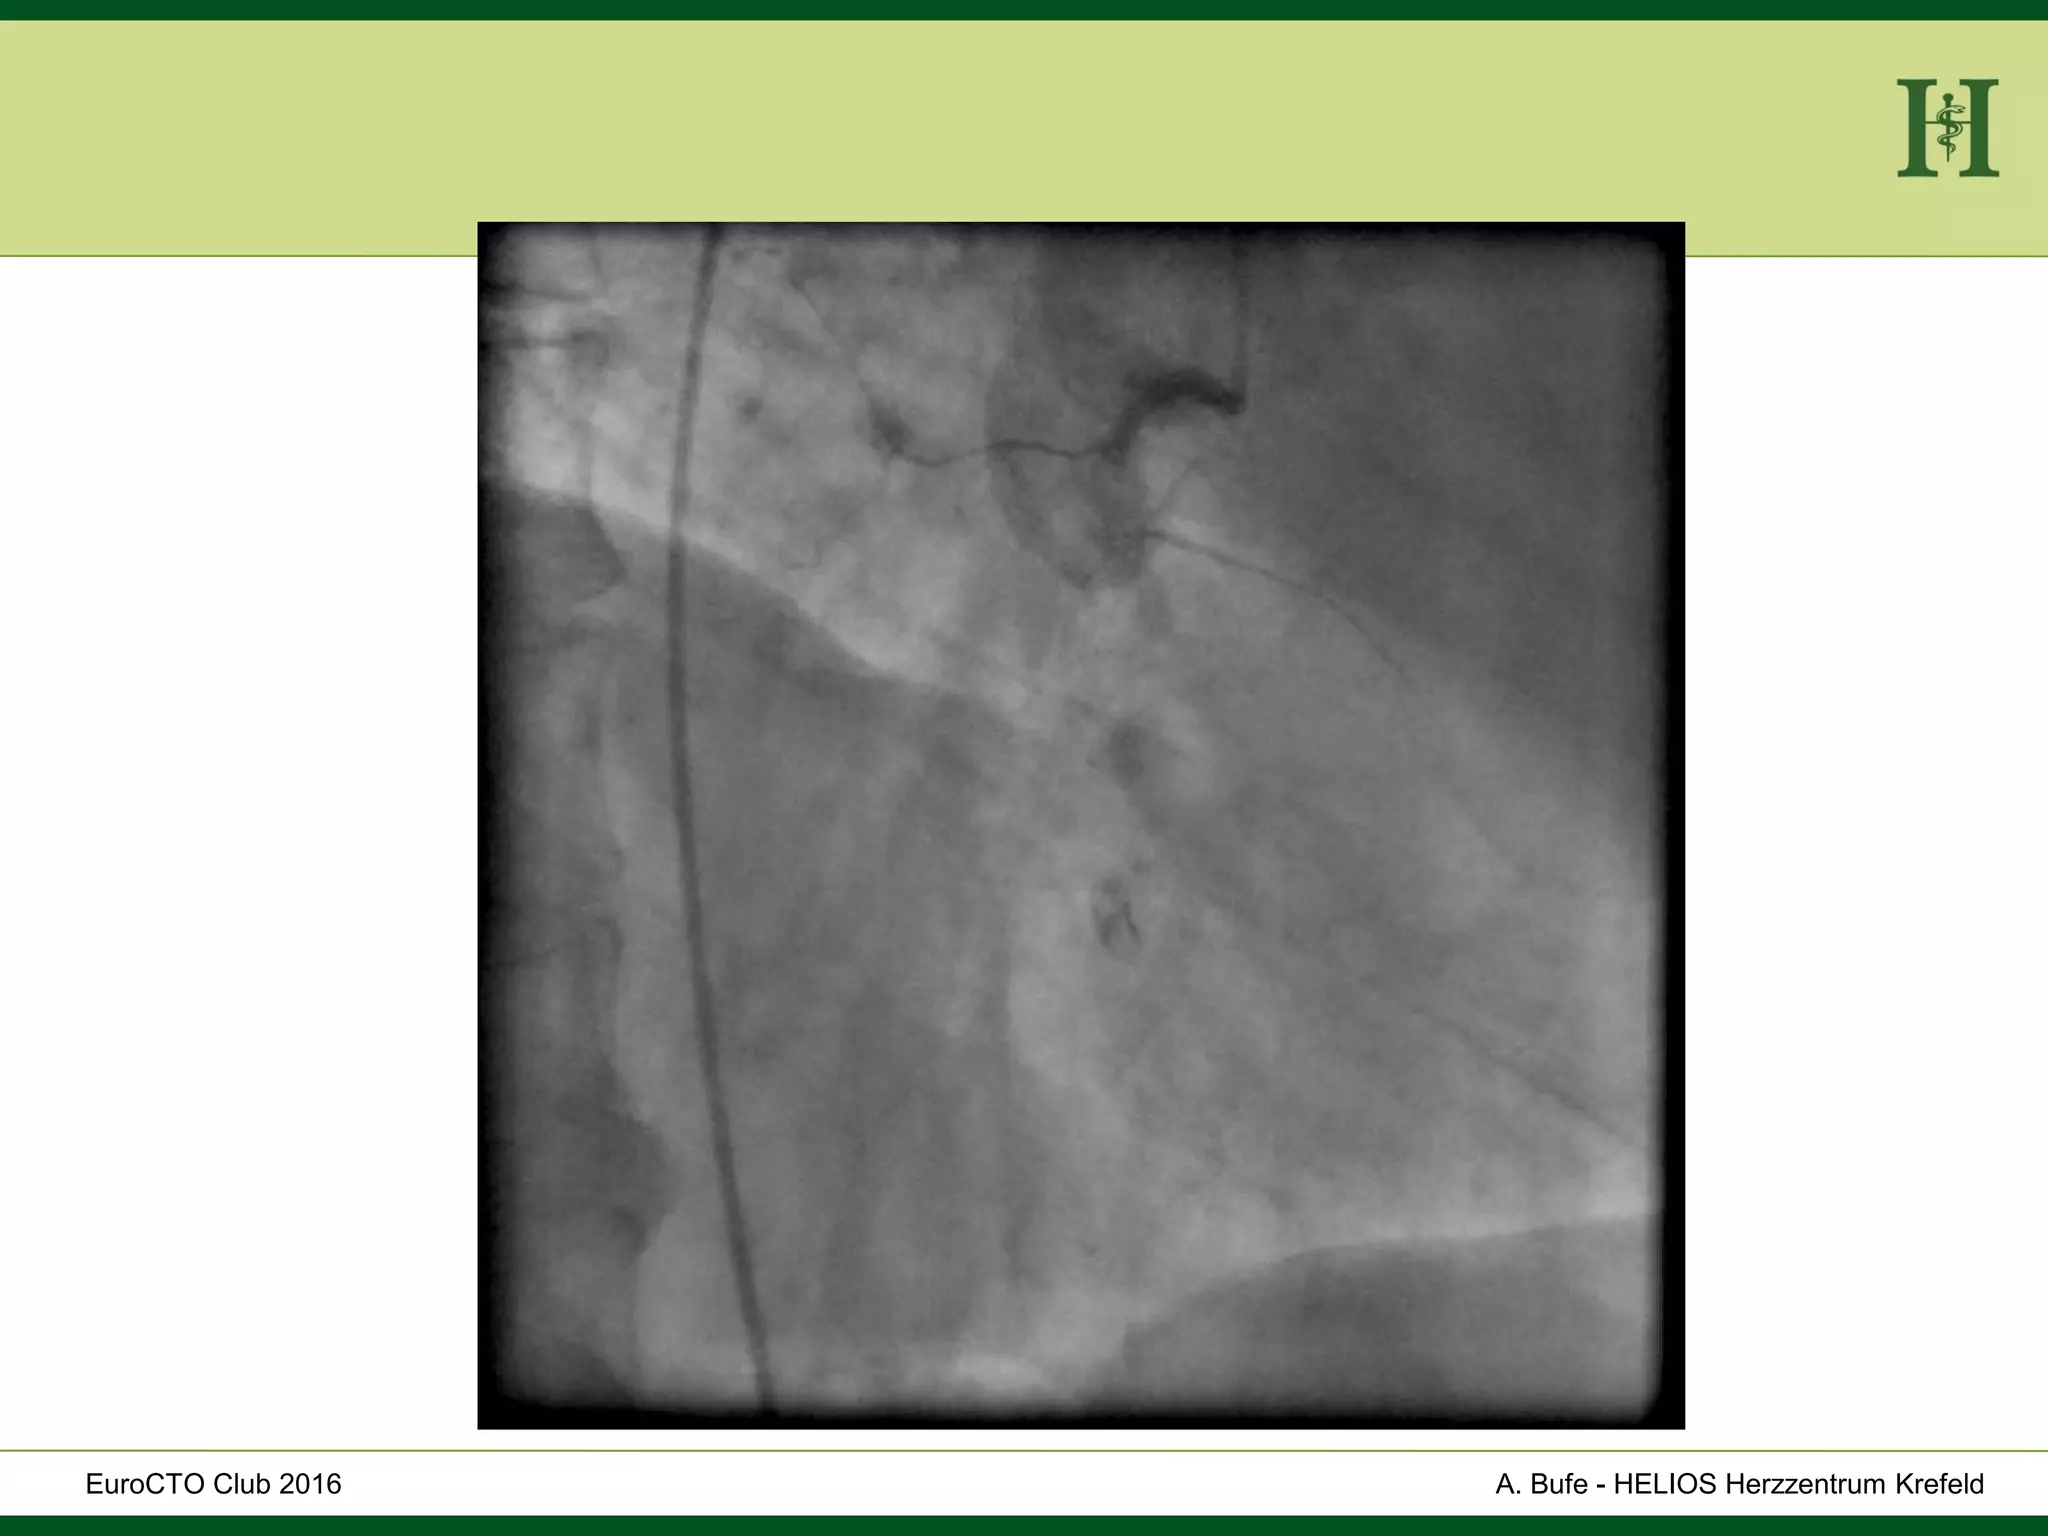

Male Patient, 55 years old

History:

 PCI 2015 with DES in LAD and in proximal RCA and

in PLD

 Angina pectoris CCS III for 7 months

 170cm, 75Kg

 RF: HLP, hypertension, smoking, HLP, familiy history

 Echo: Normal LV-Function, EF 65%

 Ischaemia inferior (MRI)